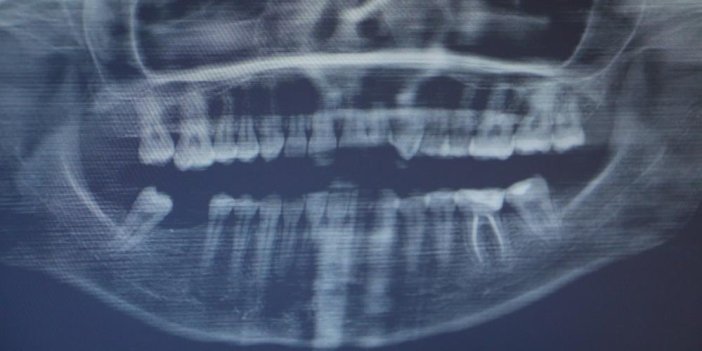

Son yıllarda yaygınlaşan implant tedavisi, Diyarbakır Ağız ve Diş Sağlığı Hastanesi’nde de uygulanmaya başlandı. Diyarbakır Ağız ve Diş Sağlığı Hastanesi Protetik Diş Tedavisi Uzmanı Seçkin Gül, implant tedavisi sürecinin yaklaşık 6 ay sürdüğünü söyledi. Lokal anestezi altında implant işleminin gerçekleştirildiğini dile getiren Gül, “Diyarbakır Ağız ve Diş Sağlığı Hastanesi’nde protez kliniğindeyiz. Hastanemizde yaklaşık 6 aydır implant tedavileri yapılmaktadır. Dental implant, diş eksikliği durumunda kaybedilen dişlerin yerine yapılan vida şeklinde titanyumdan üretilen yapay diş kökleridir. Dental implantlar, yerleştirildikleri çene kemikleriyle bütünleşerek sağlıklı bir şekilde sağlıklı bir alt yapı oluştururlar. Bunun üzerine diş yaparak hastamızın eksik olan dişlerini yerine koyarız. Tek diş eksikliğinden dişsiz hastalara kadar geniş bir alanda dental implantlar yapılmaktadır. Dental implantların iki aşaması var. Bunun ilk aşaması cerrahi aşamadır. Lokal anestezi altında implantlar çene kemiğine yerleştirilir. 2-3 ay kadar bu implantın çene kemiğiyle birleşmesi beklenir. Çene kemiğiyle bu implantlar kaynaştıktan sonra protez aşamasına geçilir. Hastamızın sonrasında implant destekli protezleri üretilerek, dişleri yerine konulmuş olur” dedi.

5 adet implant yaptıran Songül Demir adlı hasta, “Arka dişlerimin iki tarafında da eksiklik vardı. Bu nedenle implant yaptırmayı düşündüm. İmplant işlemim çok güzel geçti. 5 tane implant yaptırdım” dedi.